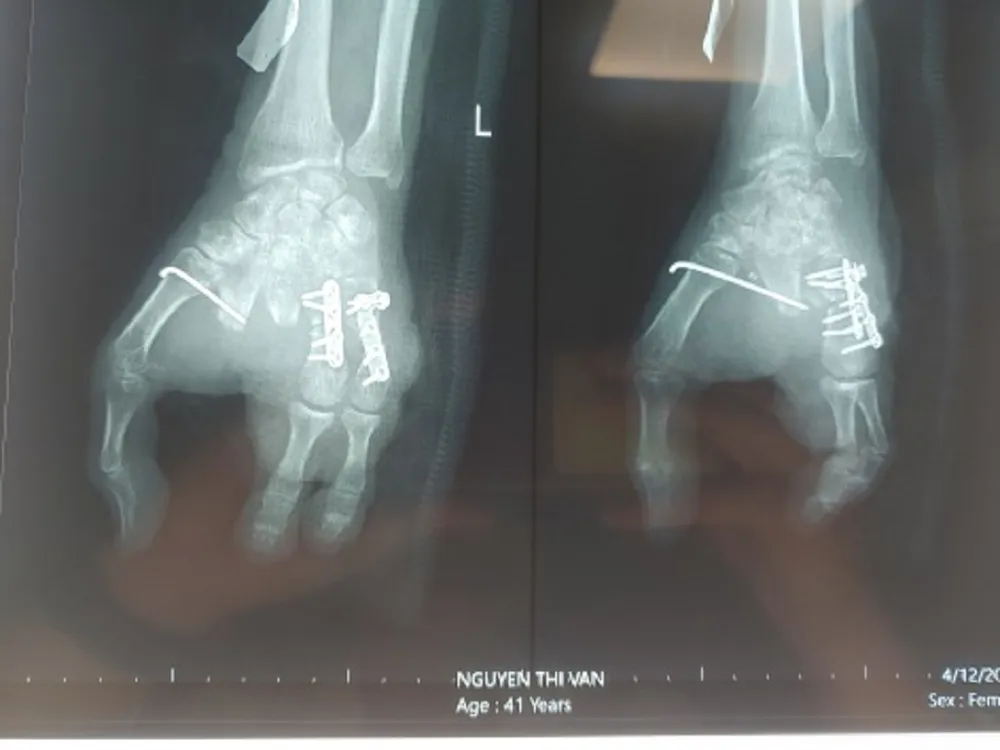

Hình chụp X-quang bàn tay trái sau khi nối ngón. Ảnh: BVCC |

Sau ba tháng, khi phần mềm tay đã ổn định, không có dấu hiệu nhiễm trùng, bệnh lý nền được kiểm soát tốt, các BS đã phẫu thuật ghép lấy ngón chân thứ 2, 3 của bàn chân trái đưa lên ngón tay thứ 4, 5 của bàn tay trái nhằm tạo cung cầm nắm cho bệnh nhân.

BS chuyên khoa 1 Võ Thành Nhơn, người trực tiếp phẫu thuật cho bệnh nhân, cho biết ca phẫu thuật kéo dài sáu giờ. Kíp mổ đã đưa ra hướng kết xương từ ngón chân lên bàn tay, khâu nối mạch máu, dây thần kinh, gân cơ từ hai ngón chân 2, 3 của bàn chân trái với mạch máu hai ngón tay thứ 4,5 của bàn tay trái, giúp phục hồi sự sống của ngón tái tạo.